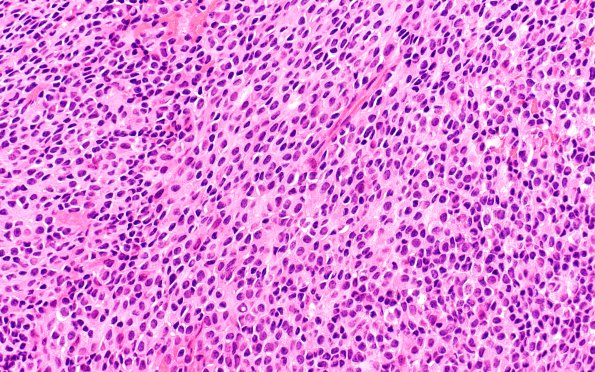

Washington University Experience | NEOPLASMS (PINEAL) | Pineal Anlage Tumor | 2B3 Pineal Anlage Tumor (Case 2) B2 H&E 40X

2B3,4 Some areas hint at a more undifferentiated pattern of growth that does not demonstrate proliferative activity expected in an embryonal growth pattern. (H&E)